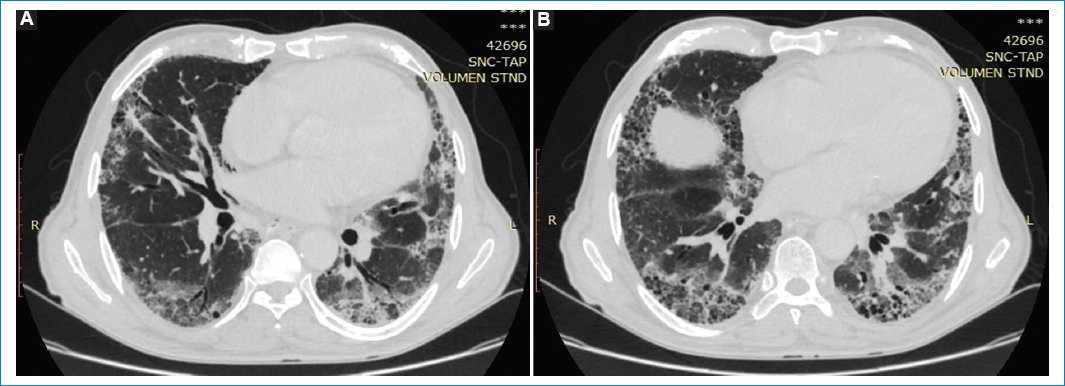

Presentamos el caso de un paciente de sexo masculino de 68 años con antecedentes de cáncer de recto con metástasis hepáticas reportadas en TC de estadificación (Fig. 1).

Figura 1. TC de tórax en ventana para evaluar parénquima pulmonar, (A) corte axial y (B) corte coronal. No se identifican particularidades en el pulmón.